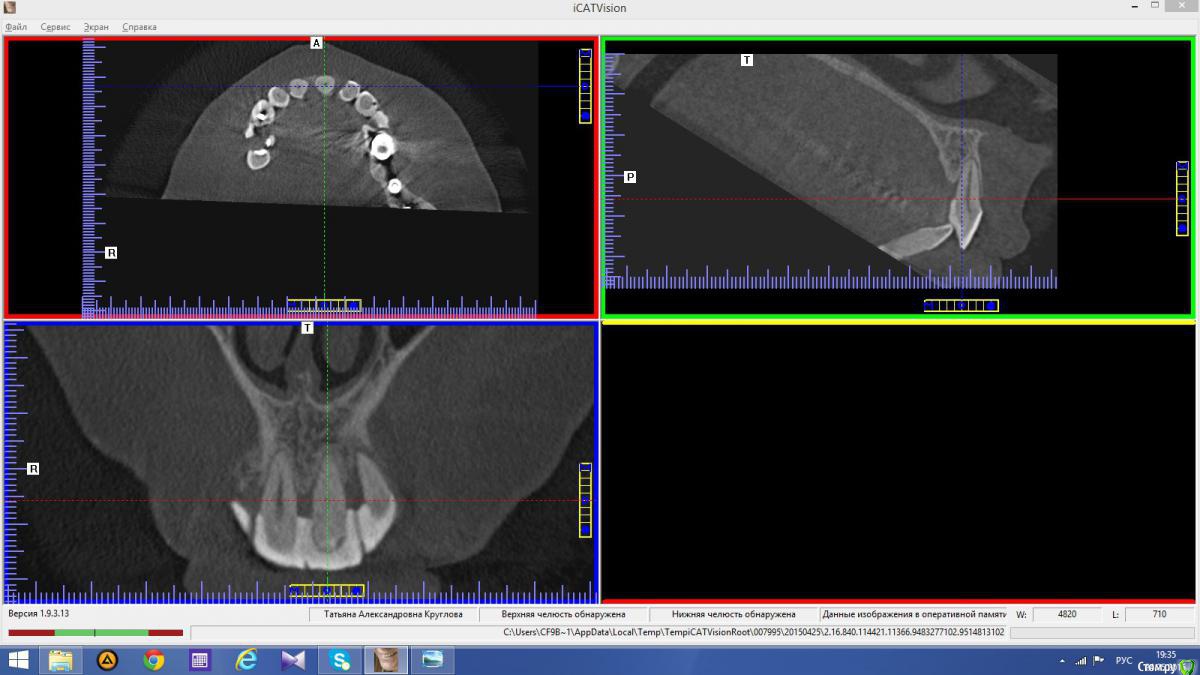

Abuk Опубликовано 24 ноября, 2015 Автор Поделиться Опубликовано 24 ноября, 2015 Снимки не могли бы показать? .все что есть готовое. Ссылка на комментарий

Abuk Опубликовано 24 ноября, 2015 Автор Поделиться Опубликовано 24 ноября, 2015 (изменено) Радикально Вы. Что оставили ей после имплантации-это инд аббатменты? На них мокап одели и нагрузили сразу? У всех был торк хороший? Или это временные абб? Что за систему использовали? В планах консоль назад, правильно я понимаю?Спасибо.увидев такую работу,сам так же подумал бы). Но там подвижность 2-3 ст. ближе к 3. Мосты болтались ,2 ки в хлам. 1 ки только стабильны. Снимал мосты,проводил кюретаж. Решил дернуть.Абатманы временные, тех. сделал на них коронки. Система анкилоз. Работа,на посл. фото, постоянная . Имплы в области 4 и по одному моляру ,консоли. Мок ап был до имплантации . По нему шаблон. Стабильность 15 -20 на 23 , остальное больше 30. Изменено 24 ноября, 2015 пользователем Abuk 1 Ссылка на комментарий